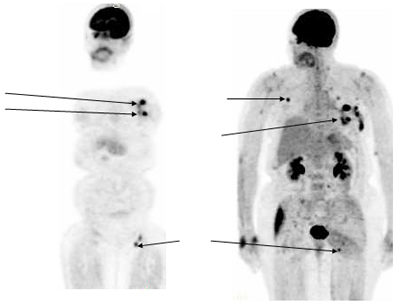

Kliničke manifestacije

Klinička slika ovisi od mjesta primarnog Tu i raširenosti (regionalne i u udaljene organe).

- Vratna regija – Limfomi se mogu javiti na vratnoj regiji i glavi kao bezbolna neobjašnjiva tvorevina, otok cervikalnih ili supraklavikularnih limfnih čvorova. Oteklina raste brzo i znatno se povećava za 1-2 nedelje. Treba napomenuti da se može pojaviti regresija i prije terapije. Opšta karakteristika uvećanih limfnih čvorova je neosjetljivost, na palpaciju tvrdi, odvojeni u početku od drugih čvorova, ali daljnim rastom konfluiraju.

- Regioni kao što su aksile, ileocekalna regija ili prepone mogu biti također mjesta primarnog Tu.

- Limfomi grudnog koša polaze iz prednjeg medijastinuma, pa mogu provocirati kašalj ili progresivnu dispneu zbog kompresije respiratornih puteva ili pleuralnog izliva, u čijem će sadržaju biti i ćelije limfoma. Ovi pacijenti zaslužuju posebnu pažnju i brzu dijagnozu. Mogu dati i sindrom kompresije vene kave.

- Abdominalni limfomi su najčešće locirani u ileocekalnoj regiji, prezentirajući se kao abdominalna masa, intestinalna opstrukcija ili intususcepcija, a može biti praćen i ascitesom.

- Limfomi kosti daju lokalne i difuzne bolove u kostima i obično su posledica diseminirane forme Tu, a primarni je na drugom mjestu.

- Meninigijalna manifestacija će biti praćena znacima povećanog intrakranijalnog pritiska ili ako je proširen Tu, može ledirati kranijalne nerve ili će izvršiti kompresiju kičmene moždine.